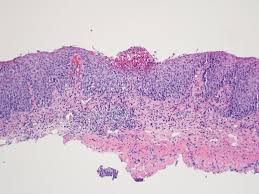

For hsv, the viral cytopathic features are usually present adjacent to the ulcer, because the virus infects the squamous epithelial cells. Virtual international pathology institute (vipi). Herpes esophagitis is one of the infectious esophagitis that usually affects immunocompromised patients. Fortschritt in der medizin, heidelberg. Welcome to the atlas of pathology website. Epidemiology it occurs as an opportunistic infection in immunocompromised patients, particularly those with aids. A cmv immunostain confirmed a diagnosis of cmv esophagitis. Report of 3 cases and review of the literature. The disease is increasingly recognized in recent decades. Within you will find microscopic explained images of basic pathology lesions along with accompanying text. Canalejo castrillero e, garcía durán f, cabello n, garcía martínez j. Herpes esophagitis is a viral infection of the esophagus caused by herpes simplex virus (hsv). We here present a case of hsv esophagitis that was presented with its characteristic features.

Differential diagnosis between herpes simplex virus (hsv) esophagitis and cytomegalovirus (cmv) esophagitis is challenging because there are many similarities and overlaps between their endoscopic features. We here present a case of hsv esophagitis that was presented with its characteristic features. Herpes esophagitis is an inflammation of the esophagus due to herpes simplex virus. Within you will find microscopic explained images of basic pathology lesions along with accompanying text. Epidemiology it occurs as an opportunistic infection in immunocompromised patients, particularly those with aids.

A cmv immunostain confirmed a diagnosis of cmv esophagitis. Causes of esophagitis include stomach acids backing up into the esophagus, infection, oral medications and allergies. For hsv, the viral cytopathic features are usually present adjacent to the ulcer, because the virus infects the squamous epithelial cells. Although hsv esophagitis is much more common in immunosuppressed individuals, it can occur in healthy persons. May cause esophageal perforation or disseminate in immunocompromised patients. Associated with cmv or hsv esophagitis in immunocompromised (see case reports below); Candida esophagitis (see the image below) is the most common type of infectious esophagitis. The majority of patients with eosinophilic esophagitis have a personal history of allergic disorders such as bronchial asthma, allergic rhinitis, allergic.